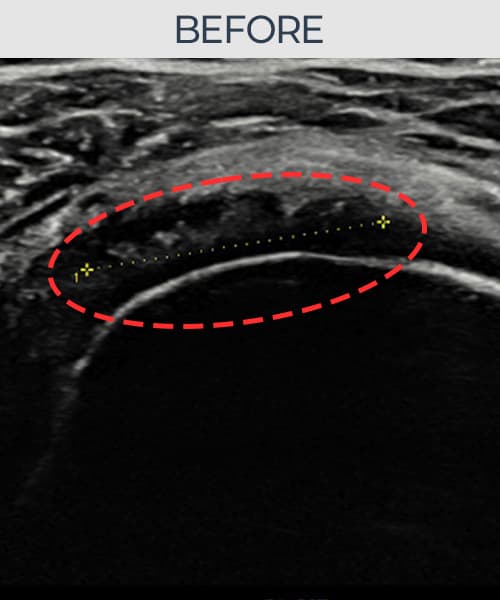

시술 전 초음파 측정 결과 파열 크기는 11mm × 6mm (힘줄 두께의 약 58% 결손)로 확인되었습니다. 시술 전 초음파에서 회전근개의 연속성 단절과 부착부 인대 두께의 현저한 감소가 확인되었습니다. 시술 후 초음파에서는 봉합된 인대의 연속성이 회복되고 부착부 두께가 정상 범위로 증가하였으며, 내부 에코 패턴도 균질하게 개선되었습니다.